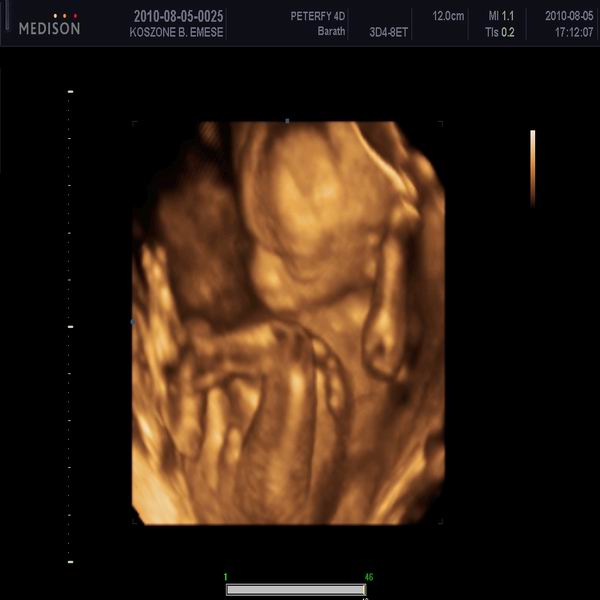

Bence: BDP 53 mm , fejvégű és 480 g

Blanka: 51mm BDP, haránt-összevissza, 450g

picit több a magzatvíz az átlagosnál állítólag, de jól vannak mindenük ép egészséges eddig:)))